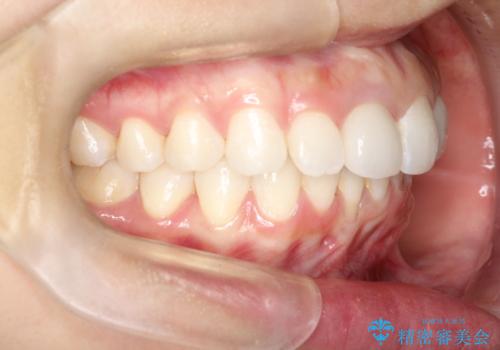

後戻りした歯並びをきれいにしたい

矯正としてはマウスピースでできましたが、患者さんの希望でワイヤー(ハーフリンガル)で矯正を行いました。

右下1が歯肉退縮していたため、アーチを拡げないように歯と歯の間を削って隙間をあけて並べています。